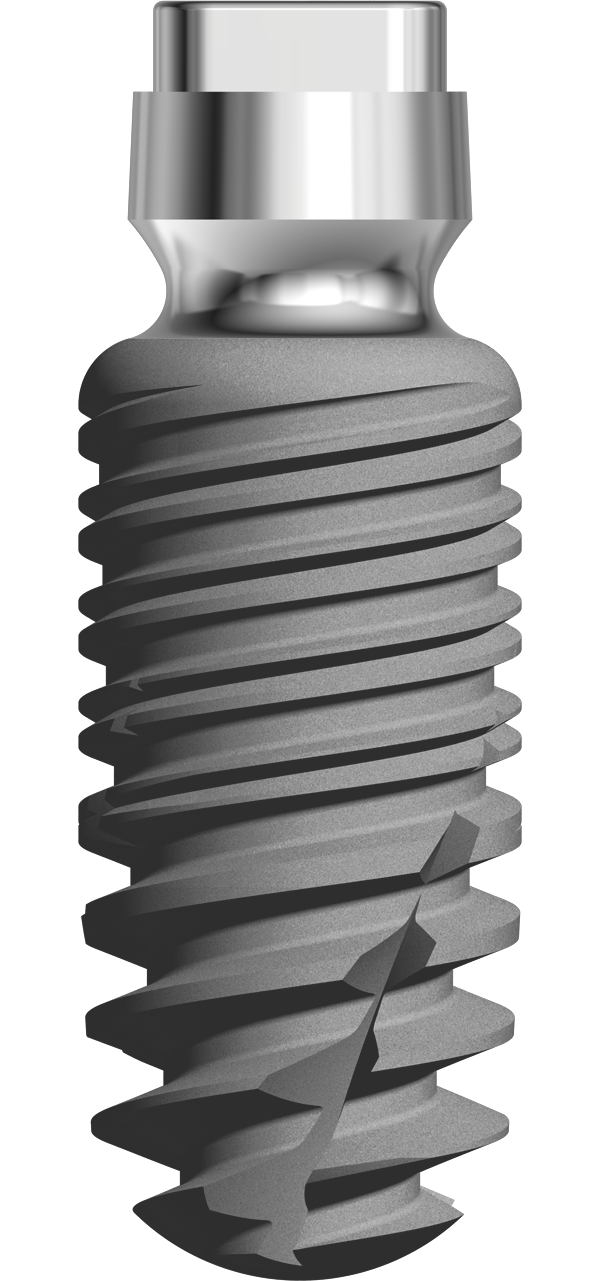

L’implant twinKon® est un implant type Tissue Level.

L’implant twinKon® est de type Tissue Level, généralement apprécié pour leur capacité à préserver le capital osseux péri-implantaire(1), mais également pour leur accessibilité prothétique en bouche. Le twinKon® est un implant qui sera particulièrement apprécié en secteur mandibulaire présentant une atrophie allant de modérée à sévère.